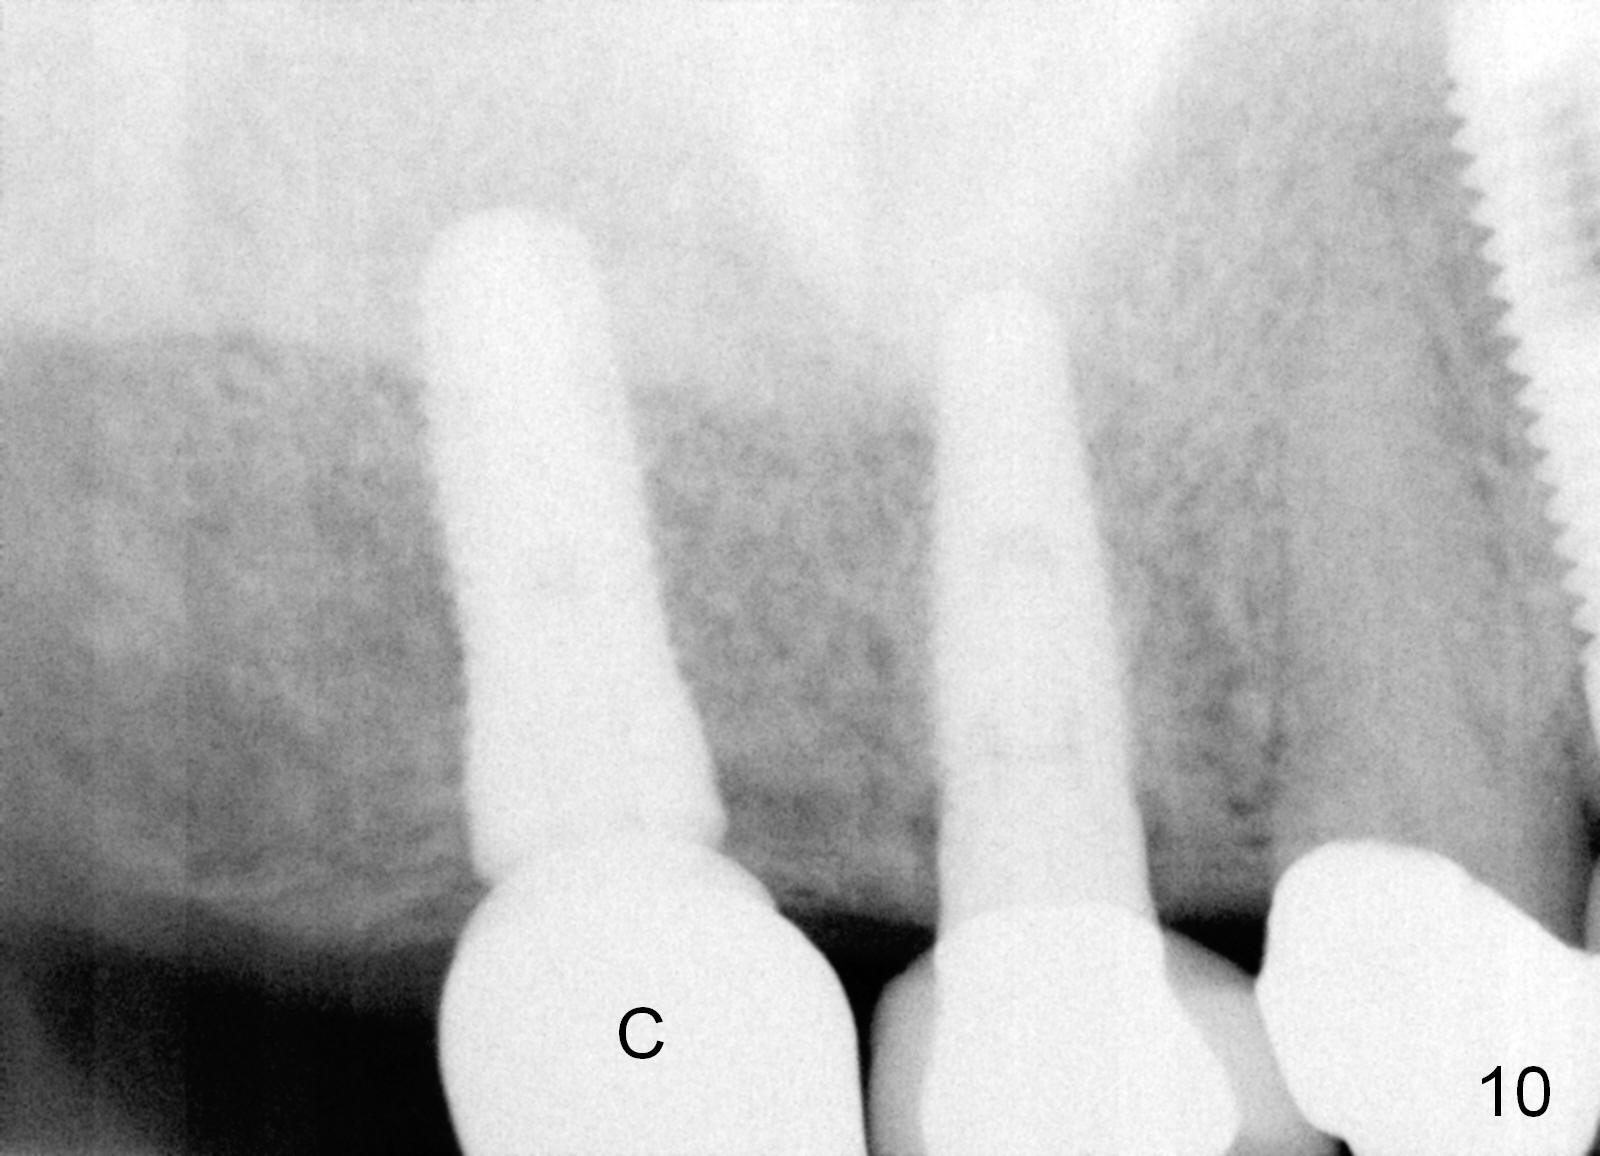

Analysis of preop PA suggests that the density of the cancellous bone is low at the site of the tooth #2. It is confirmed when a 2 mm pilot drill is used to initiate osteotomy. There is no drilling resistance once the pilot drill penetrates the cortex. A parallel pin is inserted for trajectory (Fig.1: P; 8 mm deep). The osteotomy is slightly moved distally with Lindermann bur and enlarged by inserting Bone Expanders from 2.6 to 3.8 mm at the depth of 12 mm (Fig.2). The osteotomy is then intended to move mesially and the depth is increased to 14 mm. Finally a 5.3x14 mm submerged implant is placed with insertion torque ~ 40 Ncm (Fig.3). The implant looks to have been tightly engaged into the bone (Fig.4). In one word, minimal bone removal is required for implant placement in the soft bone, particularly in the maxillary posterior region. A 8.2 mm healing abutment is placed; the flaps are closed by Chromic gut suture and perio glue (Fig.5). The wound heals normally 1 week postop (Fig.6). Fig.7 shows X-ray 3 months postop (H: healing abutment). Soft tissue looks healthy 4 months postop before (Fig.8) and after (Fig.9) removal of the healing abutment for restoration. There is no bone loss 7 months post cementation and 11 months postop (Fig.10 C: crown). It appears that bone expansion prevents bone resorption. There is no bone resorption 1 year 9 months post cementation. The implant is functioning 3 years 9 months post cementation (Fig.11).